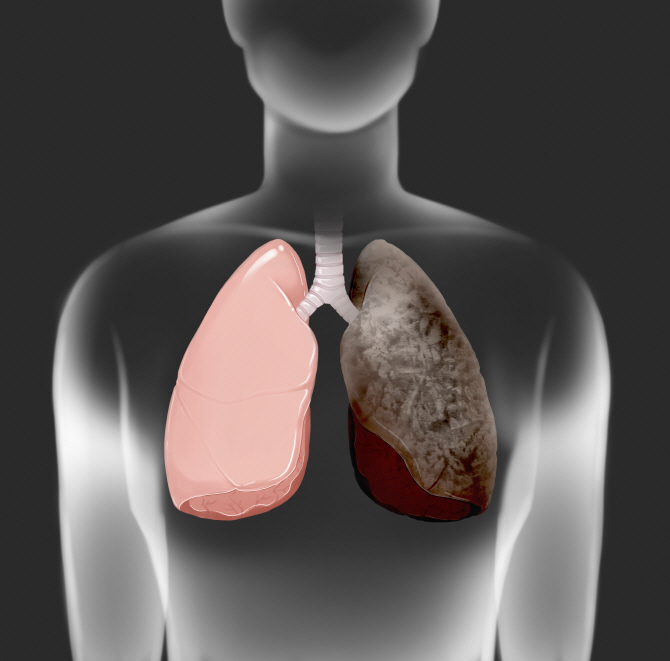

흡연은 폐암의 주요 원인으로 폐암 발생의 약 85%를 차지합니다. 폐암 발병 위험은 흡연한 담배의 개수와 흡연 기간에 따라 달라집니다. 담배를 끊은 사람은 폐암 발병 위험이 낮아지지만, 과거 흡연자는 담배를 피운 적이 없는 사람에 비해 위험이 계속 증가합니다.

흡연 외에도 대기 오염, 마리화나 사용, 담배 연기 및 간접흡연, 난방을 위한 화기 사용으로 인해 석면, 방사선, 라돈, 비소, 크롬산염 등 폐암의 알려진 위험 요인에 노출될 수 있습니다. 폐암, 특히 선암과 기관지 폐포 세포암은 결핵과 같은 다른 폐 질환으로 인한 폐의 흉터로 인해 발생하는 경우도 적지 않습니다.